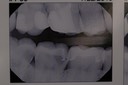

Gary Umeda #2,3 bitewing radiograph